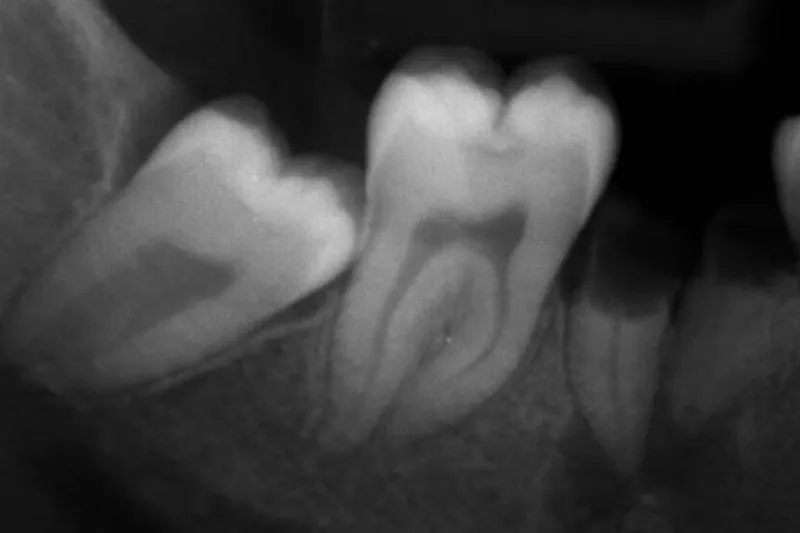

En ung asylansøger dukker op uden identifikationspapirer, og det er afgørende for den videre sagsbehandling at få oplyst, om personen er over eller under 18 år. Dette kræver en retsmedicinsk undersøgelse, og et vigtigt led heri er vurdering af visdomstændernes udviklingsstadie.

Undersøgelsen er baseret på vurdering af panoramaoptagelser fra 1.302 personer (ca. 50 af hvert køn i hver aldersgruppe fra 13 til 25 år). I alt blev 5.158 visdomstænder vurderet. 100 optagelser blev undersøgt flere gange med henblik på bestemmelse af registreringernes reproducerbarhed. Udviklingsstadiet blev registreret på en skala fra 1 til 10, hvor 10 repræsenterer en færdigdannet tand.

Resultaterne viste, at visdomstænderne udvikles hurtigere i overkæben end i underkæben, at udviklingen sker hurtigere hos mænd end hos kvinder, og at den mesiale rod på underkæbevisdomstænderne udvikles hurtigere end den distale. Der var høj grad af overensstemmelse mellem registreringerne, både når de blev foretaget af to forskellige undersøgere, og når den samme undersøger registrerede ved to forskellige lejligheder (kappa-værdier 0,86-0,95).